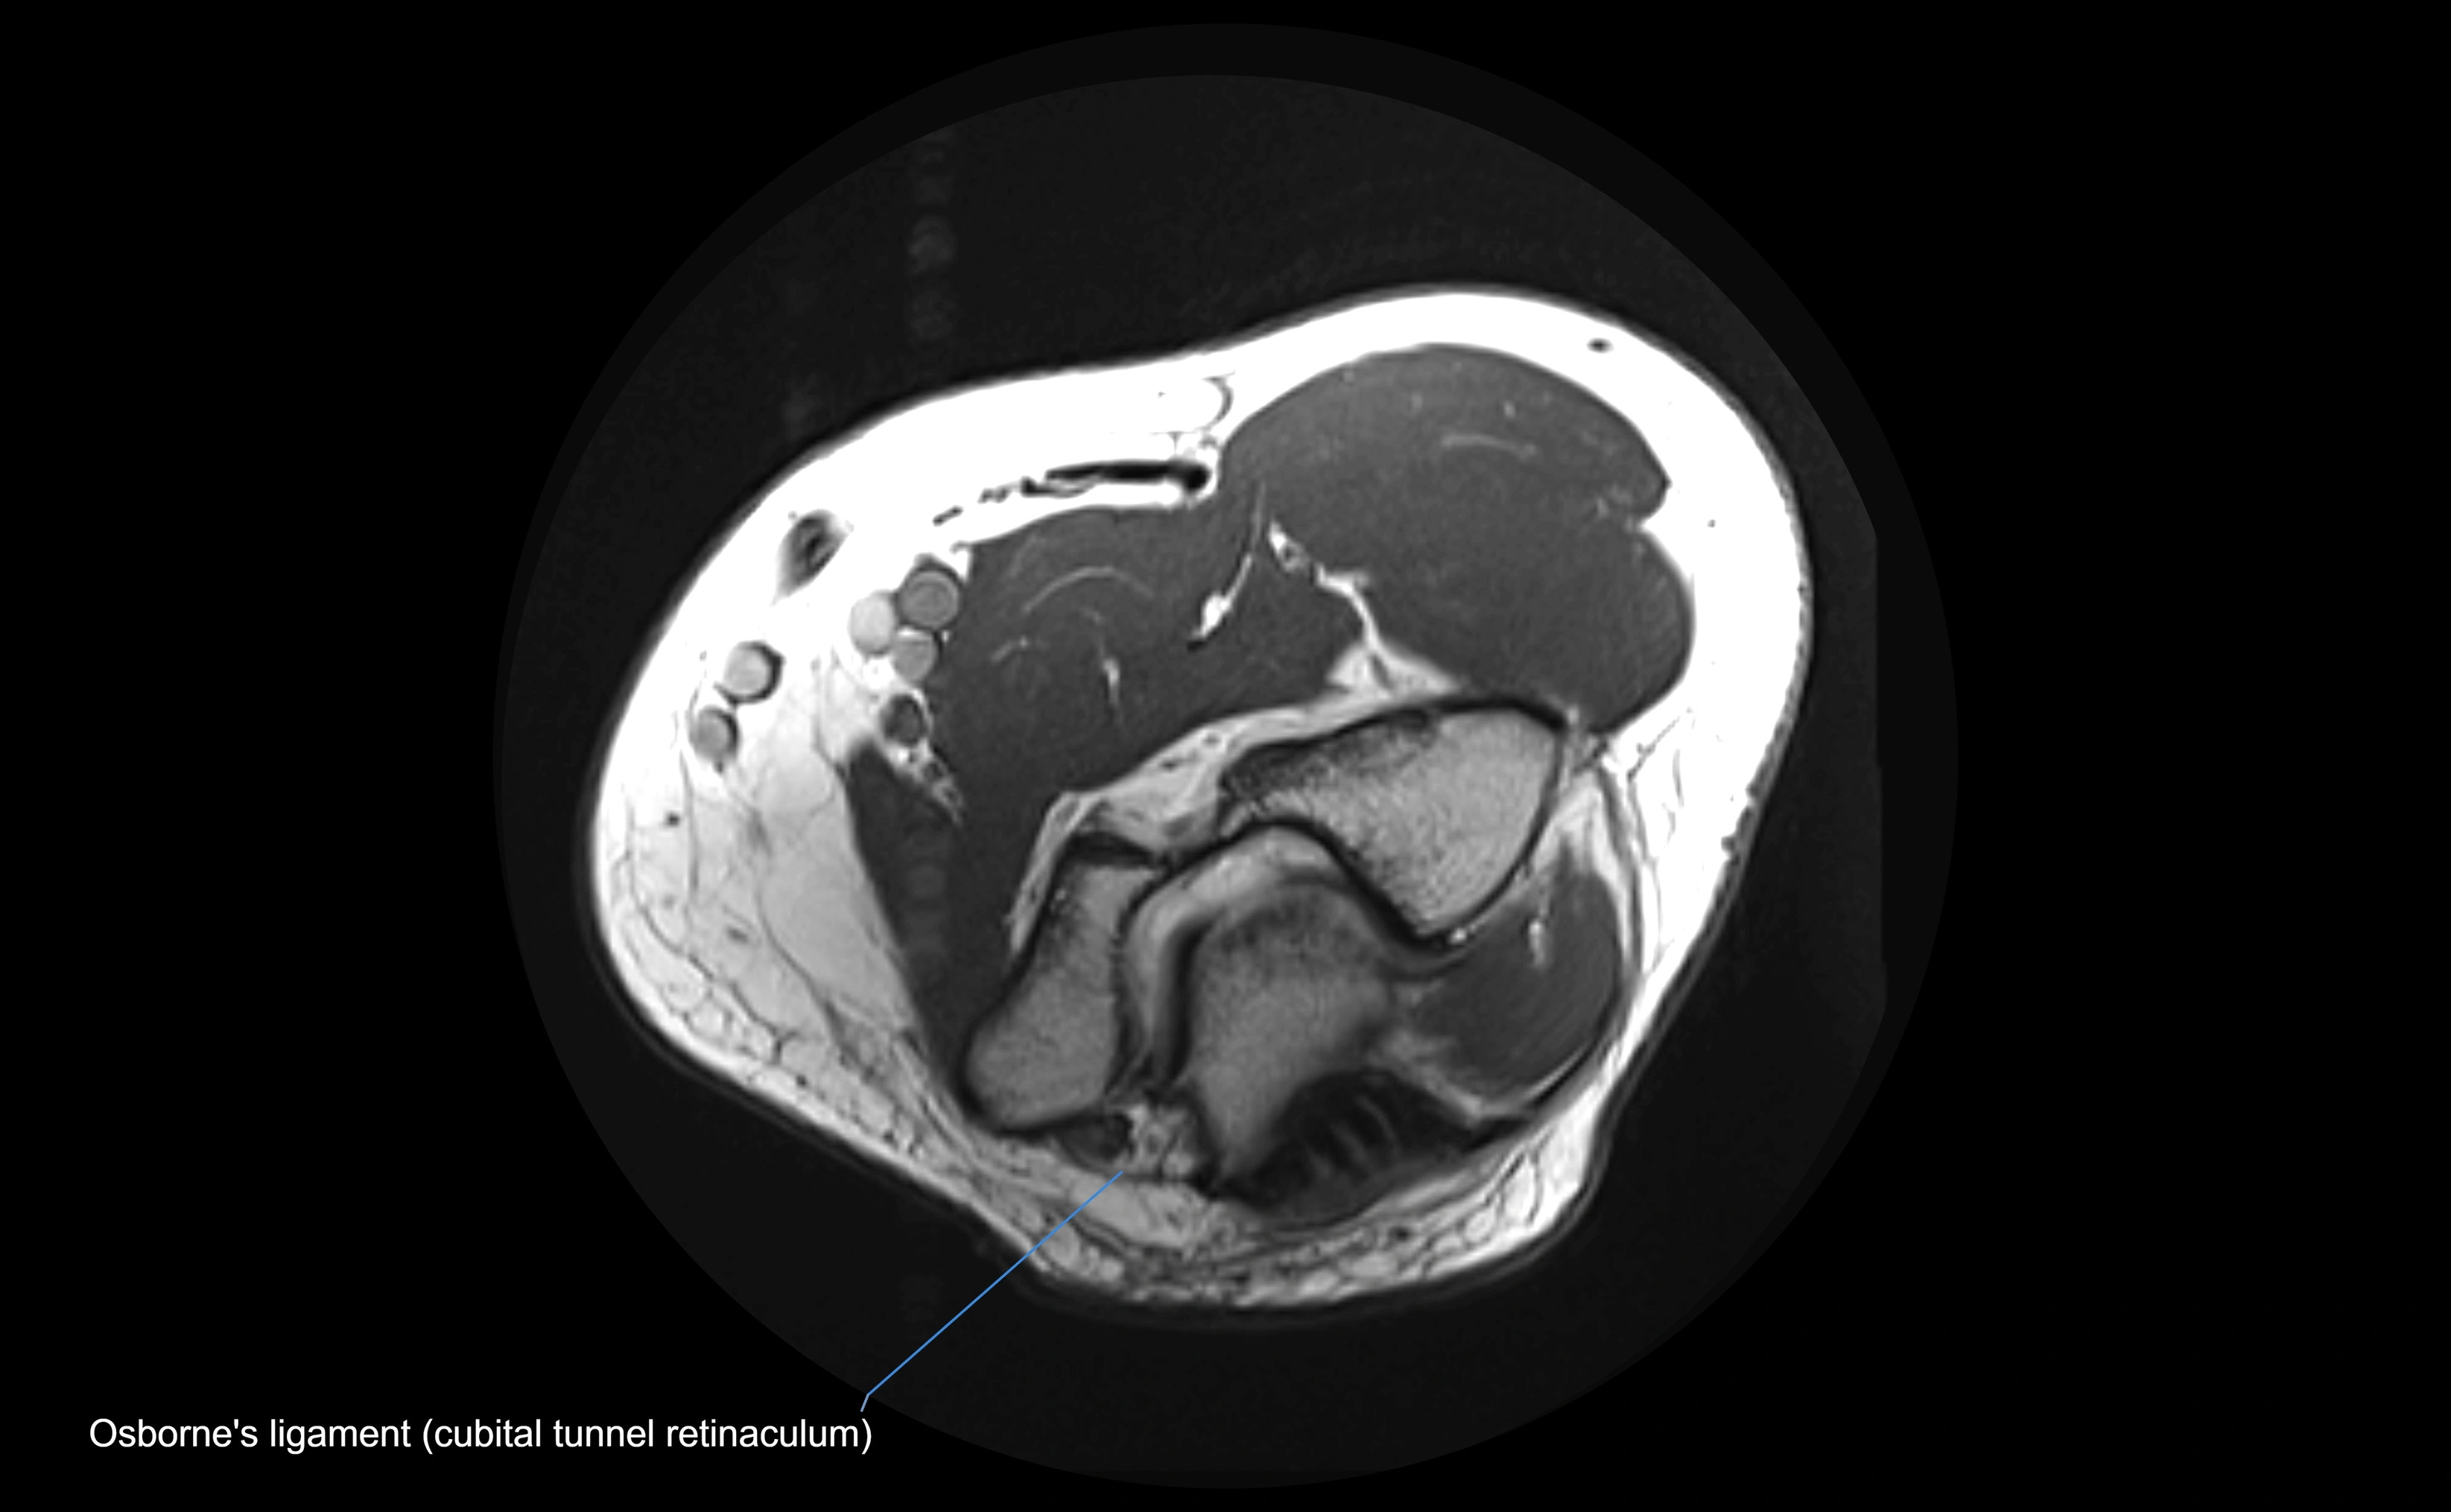

MRI Appearance

T1-weighted images:

• Ligament: low signal intensity (dark), appearing as a continuous band around the radial head.

• Adjacent fat and marrow: bright, creating contrast with the ligament.

• Thickening or disruption indicates injury or fibrosis.

• Joint capsule and synovium seen as thin low-signal lines contiguous with ligament margins.

T2-weighted images:

• Ligament: low signal (dark) with clear delineation from joint fluid.

• Fluid or edema: bright hyperintense, separating or surrounding the ligament in partial tears.

• Complete tear: discontinuity or non-visualization of ligament fibers, often with joint effusion.

STIR:

• Normal ligament: dark band encircling radial head.

• Pathology: bright hyperintense periligamentous signal suggesting edema, sprain, or partial tear.

Proton Density Fat-Saturated (PD FS):

• Normal: dark, well-defined band outlining the radial head.

• Partial tear: irregular or bright hyperintense signal within or adjacent to ligament fibers.

• Joint effusion and reactive synovitis appear bright and are well visualized.

T1 Fat-Sat Post-Contrast:

• Normal: minimal enhancement.

• Inflamed or injured ligament: focal or diffuse enhancement.

• Synovial enhancement in chronic instability or post-surgical changes.

MRI images

image